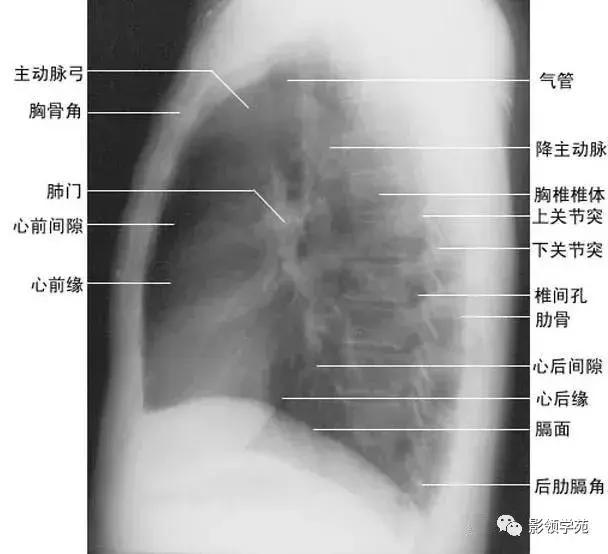

1、斜裂 一般在正位片上不能显示.在侧位片上表现为自后上斜向前下的线条状阴影:右德斜裂的后端起始于第4、5胸椎水平,斜向前下方走行,止于膈面距前缘2~3cm处,与膈顶部的水平面约成50°角;左侧斜裂后端起始点较右侧稍高,在第3~4后肋端水平,因而其倾斜度也较右饲稍大,前下端达肺的前下角处,与膈顶水平面约成60°角。叶间胸膜面通常略有弯曲,斜裂上半部稍斜向外,下半部稍斜向内,故在侧位片上可成s形。

2、横裂又称水平裂,约70%的人正、撼位胸片均可显影。在正位片上表现为右中肺野横行细线状阴影,从第6肋腋部水平自外向内延伸.并止于肺门外lcm处。可向上或向下倾斜10:左右或略成曲线;在侧位片上,横裂起白斜裂中部,向前呈水平方向走行达前胸壁。其位置的改变可作为判断肺体积变化的标志(如上图)。

(六)肺门

x线肺门指肺动脉、肺叶动脉、肺段动脉、伴行支气管以及肺静脉构成。

1、正位肺门影后前位胸片上,肺门位于两肺中野内带第2~4前肋间处,通常左侧肺门比右侧高1~2cm,两肺门的大小和密度大致相等。

(1)右肺门可分为上、下两部。上部约占113,由上肺静脉、上肺动脉及下肺动脉后回归支构成。上肺静脉下后干构成右上肺门的外缘;右肺门下部

约占213,由右下肺动脉干构成,其正常宽度不超过15mm,沿中间段支气管外缘平行向外下走行。右肺门上、下部相交形成一钝的夹角,称肺门角,正常该角顶清晰。

(2)左肺门亦分为上、下两部。上部由左肺动脉及其分支、左上叶支气管和左上肺静脉及其分支构成;下部由左下肺动脉及其分支构成,常被心影所遮盖(如下图)。

2、侧位肺门 侧位胸片上,两饲肺门阴影大部分重叠,若以侧位气管轴线为界,右肺门略信其前下,左肺门大部分在其后上。侧位肺门影前缘为右上肺静脉干形成的椭圆形阴影,前后径为2cm左右;中间纵行透亮区为气管及气管分叉,其内圆形透亮影表示支气管开口,右侧在上,左侧居下;后上缘为左肺动脉弓,下缘由两下肺动脉构成下行的树枝状影。因此,侧位肺门影似一尾巴拖长的“逗号”(如上右图):